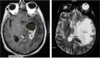

Intracerebral Hemorrhage

Intracerebral Hemorrhage